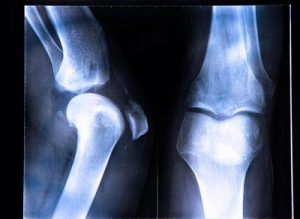

当出现前交叉韧带撕裂,患者会出现行走困难的情况,日常生活也会受到影响。而前交叉韧带撕裂多发生于运动损伤,运动员中也有很多出现前交叉韧带撕裂的情况,患者通常会选择前交叉韧带重建手术,帮助治愈韧带,但是手术带来的后遗症也是患者需要了解的。

1.任何手术都有风险,前交叉韧带重建手术也不例外。在进行前交叉韧带重建手术后,患者身上最经常出现的后遗症就是肌肉萎缩。而这部分患者需要进行康复训练,帮助按摩肌肉,同时锻炼身体的各个部位,才能够减轻后遗症,帮助行走,恢复身体健康。

3.前交叉韧带重建手术也有可能带来肌后侧肌肉群无力。当患者出现肌肉群无力后,往往行走困难,甚至站立不稳。因此患者在出现后遗症之后,可以选择康复治疗。同时有可以辅助以药物治疗,在医生的指导下用药,帮助肌肉群更好地恢复功能,保证身体的健康。

如果患者本身需要运动,并且前交叉韧带损伤十分严重的,就需要进行前交叉韧带重建手术,而通过手术,可以帮助患者治愈韧带出现的撕裂情况,让患者恢复健康。但是在术后,患者也要注意日常护理,避免创口感染,出现发炎的情况。